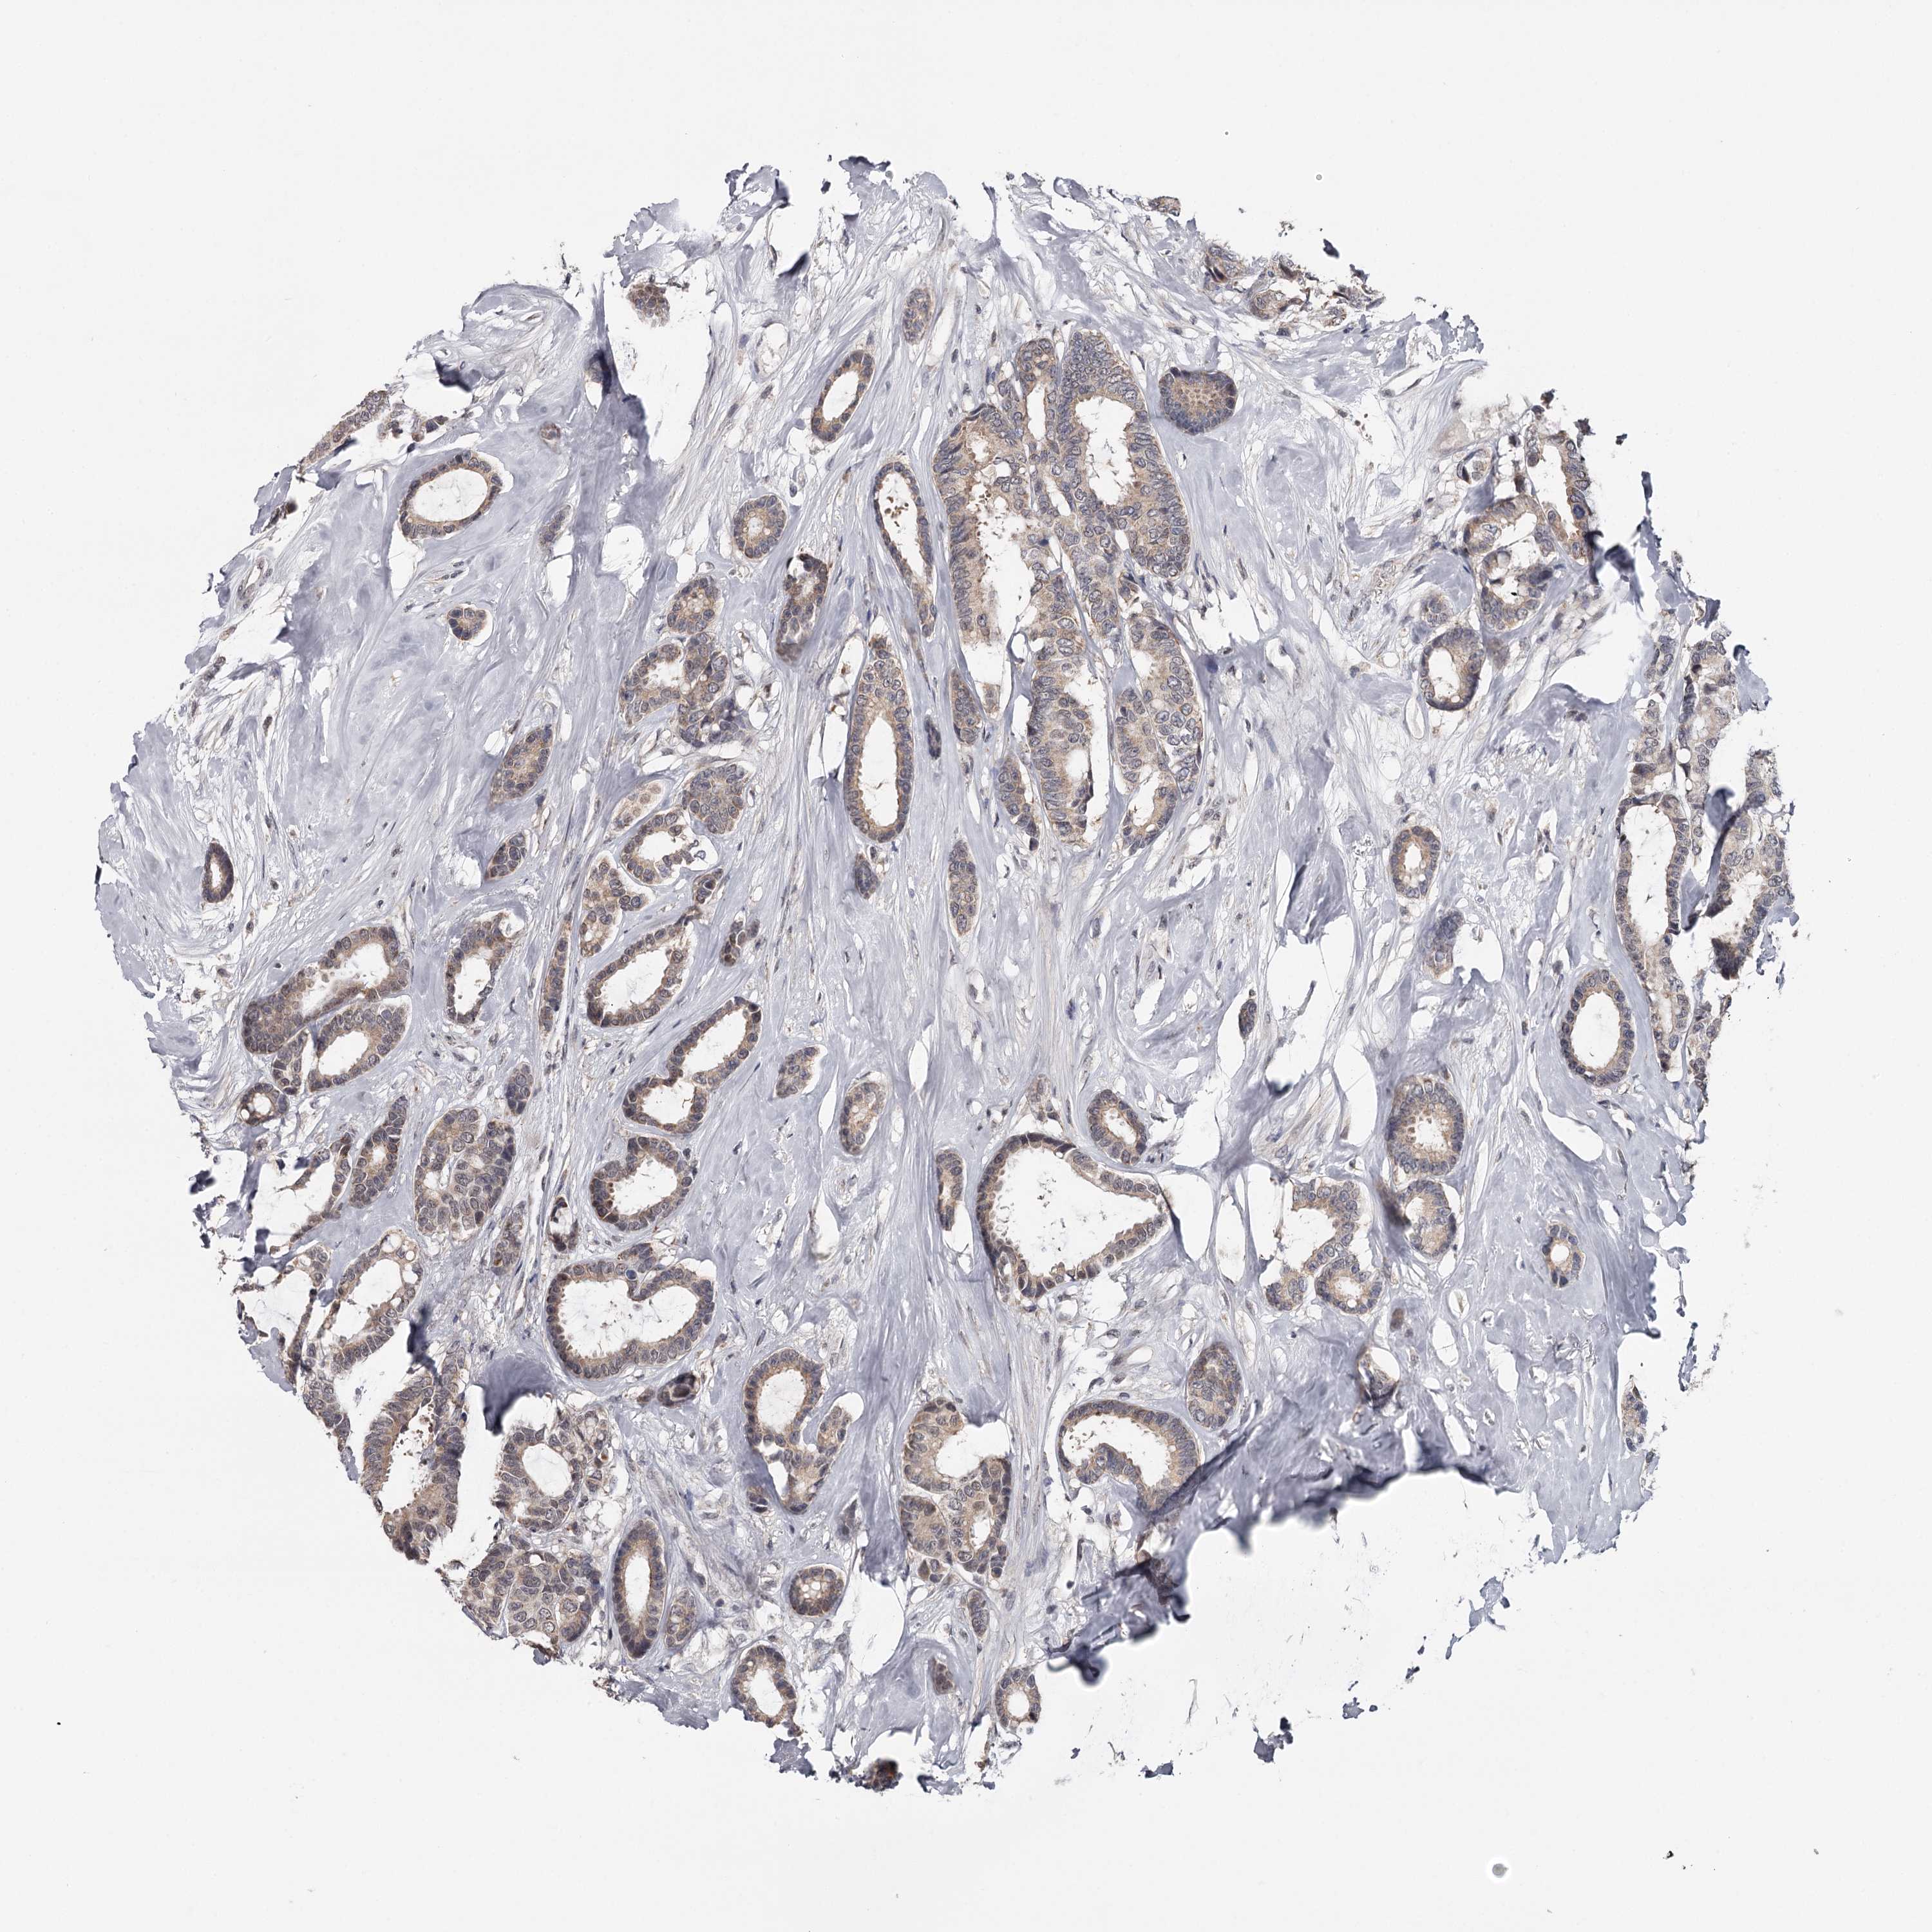

CANCER BREAST CANCER Show tissue menu

BRCA TCGA BRCA VALIDATION PROTEIN EXPRESSION